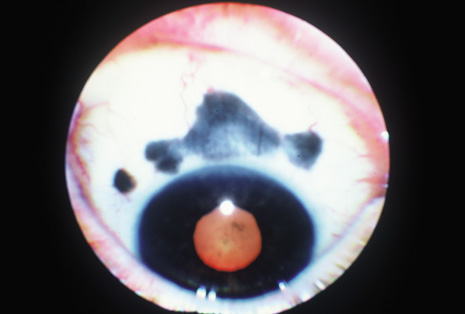

Although keratocentesis had been advocated historically as a treatment for active uveitis, it lost the attention of ophthalmologists until 1919, when Bruckner3 first examined the aqueous humor for diagnostic purposes. Laboratory techniques were revolutionized in the 20th century in areas such as: (a) evaluating very small aliquots of fluid (0.2 to 0.3 mL of aqueous or vitreous), and (b) identifying specific microbial organisms and the predominance of other cell types, antibodies, and proteins in these fluids (Figs. 1, 2, 3, 4, 5, and 6). These advancements have led to the development of diagnostic paracentesis for sight-threatening ocular inflammations that are difficult to diagnose. Witmer4 and O'Connor5 have provided strong evidence that samples of the aqueous humor reflect the antibody-producing capabilities of the iris and ciliary body, particularly when more specific antibody per unit of gamma globulin can be found on the aqueous humor than in the blood of the same patient.6–8 These determinations may be highly significant when one considers the fact that diseased tissue is being bathed in an antibody-containing fluid that is elaborated locally. For instance, in the case shown in Figure 1, the immunofluorescent antibody titer to toxoplasmosis is four times greater in the vitreous aspirate at the time of vitrectomy for repair of retinal detachment than in the plasma. These same considerations have long been recognized in syphilis of the central nervous system, wherein specific antibodies may be present in the cerebrospinal fluid but not in the blood. This is also the case with an unusual presentation of ocular coccidioidomycosis9 or toxocariasis.

Many forms of uveitis are characterized by specific types of inflammatory cells. Usually, however, one encounters mixtures of cell types in any given specimen, with the relative percentages of lymphocytes and polymorphonuclear leukocytes varying. There may be unusual numbers of eosinophils, or macrophages laden with lens material may be present. Thus, an enumeration of the cells and a careful analysis of their structure can be useful as a diagnostic aid (Figs. 7, 8, 9, 10, 11, 12, 13, 14, 15, 16, 17, 18, 19, and 20). Figure 15 demonstrates eosinophils that were aspirated from the anterior chamber of a patient with Toxocara canis endophthalmitis. Figure 12 demonstrates malignant cell infiltrate from the vitreous, showing the stained presence of monoclonal light chains being elaborated in the cytoplasm. Interleukin-10, detectable in the vitreous of intraocular lymphoma patients, is also directly indicative of both the clinical activity and the number of malignant cells as observed by cytopathology.

Precise identification and culture of bacterial and fungal pathogens from both the aqueous humor and the vitreous fluid can be obtained. Gram's stain and Giemsa's stain smears of centrifuged specimens from the aqueous humor and the vitreous humor frequently demonstrate the bacterial or fungal causative agent. Attempts to isolate bacteria and fungi and to identify them on Gram's stain or Giemsa's stain smears have been most rewarding in the following cases: (a) postoperative endophthalmitis, (b) infection after a penetrating injury of the eye, (c) drug abuse patients with endogenous endophthalmitis (Figs. 21, 22, 23, 24, and 25), (d) patients receiving hyperalimentation, and (4) patients who are immunocompromised as a result of exogenous immunosuppressive agents.